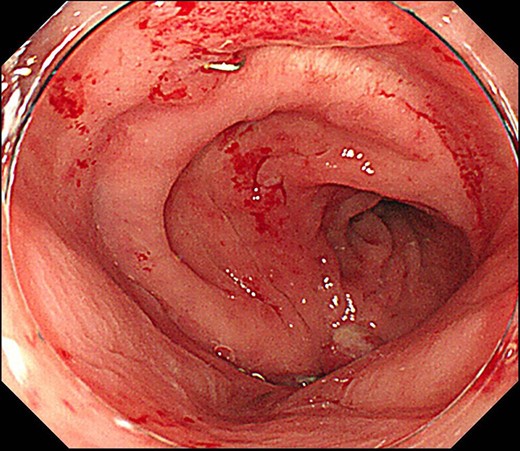

Case 1 was a 71-year-old man with a BMI of 29.7 kg/m2. Laparoscopic low anterior resection (LAR) and ileostomy was performed for rectal cancer in 2017 years. Postoperative fever and lower abdominal pain were noted, and colonoscopy was performed, and anastomotic leakage was noted with a correction of about 1/2 around the 6 o’clock direction of the anastomotic region, and fistula and formation of a large abscess cavity. After identification (Fig. 1), a tube was inserted for drainage and conservative treatment was performed. The patient was discharged on POD 46. Four months after the operation, marked improvement in the abscess cavity was noted but still remained (Fig. 2a and b). Anastomotic leakage was almost improved by colonoscopy at 17 months after surgery, but at the preference of the patient we performed colostomy 22 months after surgery (Fig. 3). It took a long time to improve intestinal movement of the colon because the large intestinal tract had not been used for a long time, and conservative treatment was performed using a nasogastric tube for paralytic ileus. Diet was initiated 7 days after surgery, and the patient was discharged from the hospital 14 days after surgery. The Wexner score [2] was 19 points one month after closure, 17 points 3 months after the operation and 16 points after 6 months after the operation, and severe anal dysfunction was observed, but gradually improved.

Colonoscopy shows that the suture failure has improved with only a slight depression.